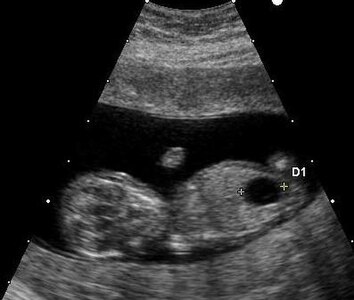

Ultrasound imaging can be used to screen for Down syndrome. Findings that indicate increased risk when seen at 14 to 24 weeks of gestation include a small or no nasal bone, large ventricles, nuchal fold thickness, and an abnormal right subclavian artery, among others.[89] The presence or absence of many markers is more accurate.[89] Increased fetal nuchal translucency (NT) indicates an increased risk of Down syndrome picking up 75–80% of cases and being falsely positive in 6%.[90]

Ultrasound of fetus with Down syndrome showing a large bladder

Enlarged NT and absent nasal bone in a fetus at 11 weeks with Down syndrome